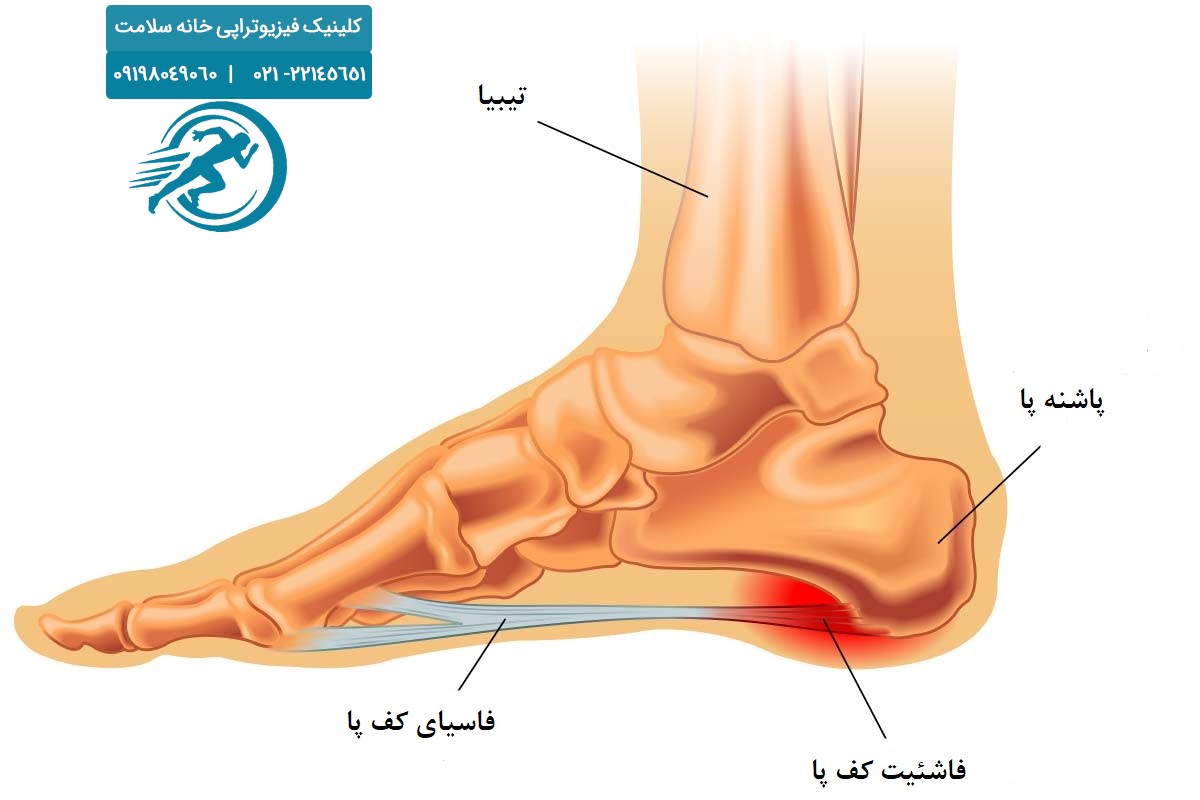

خار پاشنه یا فاشئیت پلانتار چیست؟

خار پاشنه یک زائده استخوانی کوچک است که در قسمت زیرین پاشنه ایجاد میشود. بسیاری از افراد این مشکل را با التهاب فاشیای کف پا یا همان فاشئیت پلانتار تجربه میکنند. درواقع، اغلب درد پاشنه ناشی از التهاب و کشش بیشازحد این رباط کف پایی است، نه صرفاً وجود خار استخوانی.

عواملی مانند ایستادن طولانیمدت، استفاده از کفشهای نامناسب، اضافه وزن و فعالیتهای ورزشی سنگین از دلایل اصلی بروز این مشکل هستند. اگر درمان خار پاشنه به موقع آغاز نشود، درد و محدودیت حرکتی افزایش یافته و زندگی روزمره بیمار تحتتأثیر قرار میگیرد.

علل خار پاشنه (فاشئیت پلانتار)

خار پاشنه یا فاشئیت پلانتار معمولاً به دلیل فشار و کشش بیشازحد بر روی فاشیای کف پا ایجاد میشود. این فشار مداوم باعث التهاب در محل اتصال فاشیا به استخوان پاشنه و در برخی موارد تشکیل زائده استخوانی (خار پاشنه) میگردد. مهمترین علل بروز این عارضه عبارتاند از: